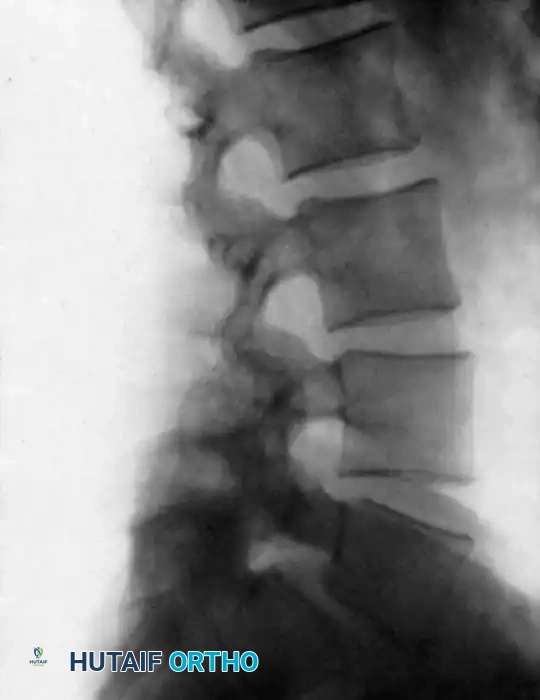

Accurate visual identification of a specific vertebral level is notoriously difficult in the dorsal and lumbar spine, except when the sacrum can be definitively exposed and identified. Despite anatomical peculiarities of spinous processes, laminae, and articular facets, relying solely on visual landmarks is fraught with error.

We strongly recommend a standardized method consisting of the radiographic identification of a radiopaque marker clamped securely to a spinous process within the operative field. The closer to the base of the spinous process the marker is inserted, the more accurate the identification. Cross-table lateral radiographs or anteroposterior (AP) fluoroscopic images taken on the operating table must be compared meticulously with high-quality preoperative radiographs.